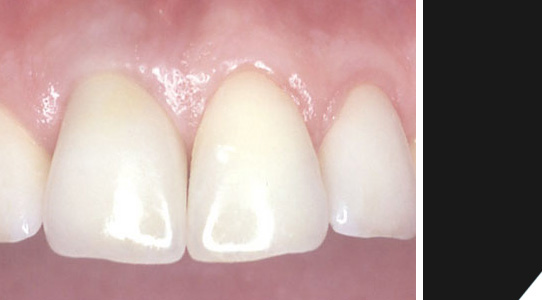

Hier sehen Sie das Beispiel eines Patienten mit Sportverletzung. Ein Rest des oberen rechten Schneidezahns ist noch vorhanden.

Zum Schluß erhält man ein optimales Ergebnis. Tragekomfort und Ästhetik lassen keine Wünsche offen. Der Zahnersatz ist praktisch nicht von natürlichen Zähnen zu unterscheiden.